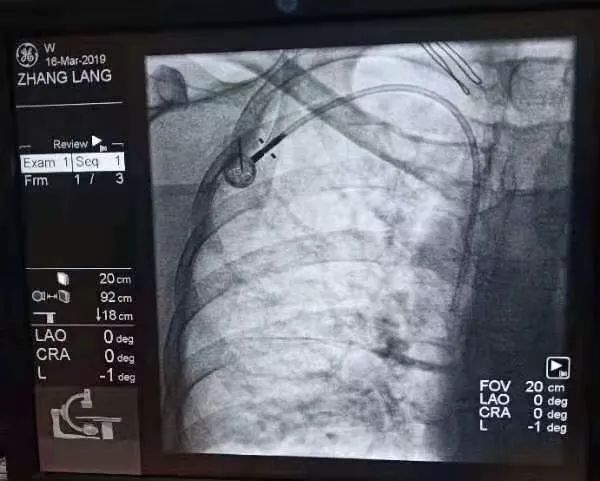

而輸液港port植入技術(shù)就可以解決這一難題。上周六,來自港閘區(qū)的張女士就在我院接受了靜脈輸液港植入術(shù)。來自上海六院的王永剛主任和瑞慈上海腫瘤中心孫英豪主任共同為患者進(jìn)行了手術(shù),輸液港完美植入患者體內(nèi),張女士術(shù)后很快就適應(yīng)了新伙伴的存在。